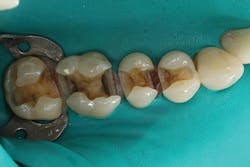

Figure 3: A segmented matrix setup with two Composi-Tight 3D-XR rings (Garrison Dental Solutions) and a 5.5-mm Slick Band (Garrison Dental Solutions) was placed on No. 3. Then, the preparation enamel was selectively etched with 37% phosphoric acid etchant with benzalkonium chloride (Bisco) for 20 seconds.

Figure 4: A universal adhesive was scrubbed for 20 seconds, air thinned, and light cured for 10 seconds. A layer of Tetric EvoFlow Bulk Fill was placed up to the proximal box and to the pulpal floor, then light cured for 10 seconds. After light curing, the bulk-fill composite exhibited a dentinlike opacity, helping to mask the discolored dentin.